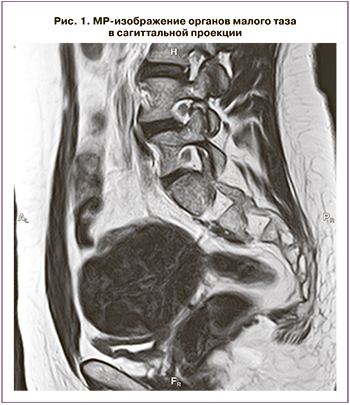

Магнитно-резонансная томография (МРТ) органов малого таза выполнена в трех проекциях в режимах Т1, Т2, DWI с использованием функции подавления сигнала от жировой ткани на фоне артефактов от перистальтики кишечника. Выявлено: матка в типичном месте не визуализируется. В полости малого таза, справа, визуализируется вытянутая мягкотканная структура с четкими неровными контурами. Общие размеры 0,9×6,0 см с наличием на уровне передних отделов узлового образования размерами 1,4×1,9 см. Схожее по МР-характеристикам мягкотканное включение слева, с наличием двух узлов, размерами 6,9×8,6×6,5 см и 2,0×1,6×2,7 см. Яичники расположены выше описанных мягкотканных структур, размерами: справа – 1,2×1,9×2,0 см, слева – 1,3×2,1×1,2 см. Капсула яичников не утолщена, строма неоднородного пониженного МР-сигнала, фолликулы не определяются (рис. 1, 2).